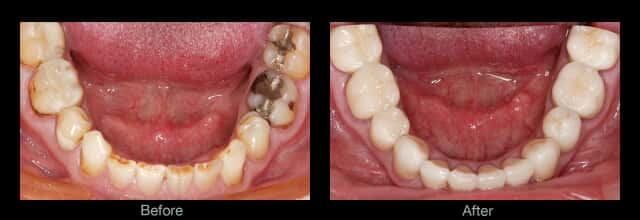

Inlays & Onlays